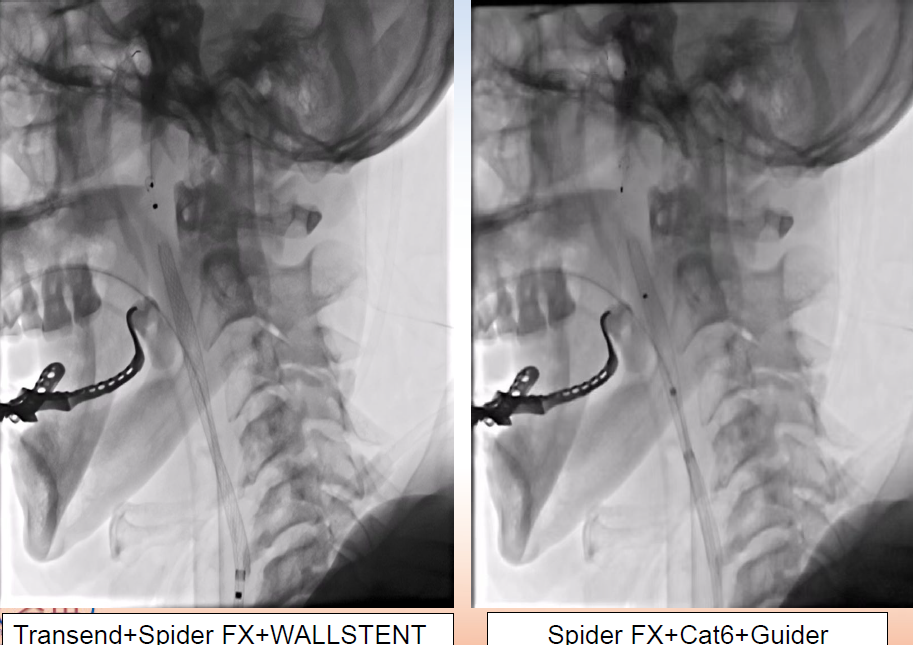

手术过程

在Synchro微导丝与Rebar-18支架导管的辅助下顺利超选上去,借助Transend导丝使用球囊穿梭技术将Sprinter(3*15)球囊装入血管真腔中。

过程影像

病历夹什么径技·第152期|串联营病历夹:川陕大营_https://www.jmylbn.com_新闻资讯_第83张

病历夹什么径技·第152期|串联营病历夹:川陕大营_https://www.jmylbn.com_新闻资讯_第84张

<<滑动查看下一张图片>>

由于guiding通过失败所以先处理近端,将Spider FX(5)保护伞置入进行了远端保护,近端放置了WALLSTENT支架,然后收伞,顺势将guider通过,结果其无法到达远端。

病历夹什么径技·第152期|串联营病历夹:川陕大营_https://www.jmylbn.com_新闻资讯_第85张

病历夹什么径技·第152期|串联营病历夹:川陕大营_https://www.jmylbn.com_新闻资讯_第86张

狭窄段用四个球囊后扩张,将cat6推过狭窄段,发现可能存在远端栓塞,因此将guider退了一下。